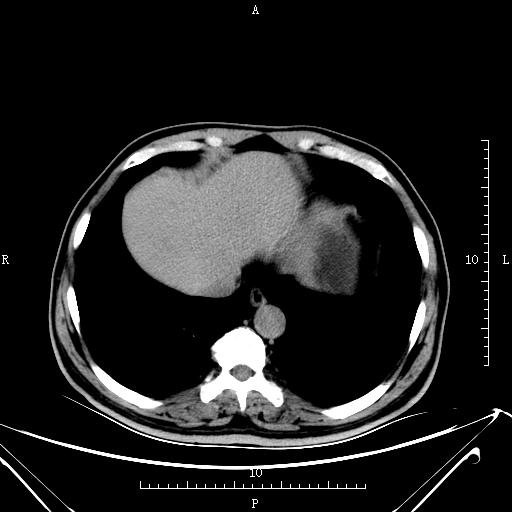

CT53350:男,68岁,上腹部疼痛1周,彩超示:胰腺占位。

男,68岁,上腹部疼痛1周,彩超示:胰腺占位。

胰腺外形欠规则,体部见低密度占位,中央区坏死,肿块轻度强化。考虑胰腺癌。

胰腺近胰腺颈部局部隆突出弱强化的占位,胰尾部萎缩,胰腺癌应该是没问题。

胰腺外形不规则,胰腺体部见低密度占位,体部中央区见坏死,增强:肿块及坏死部分未见明显强化。脾大。考虑:胰体癌。脾大。

胰体癌。